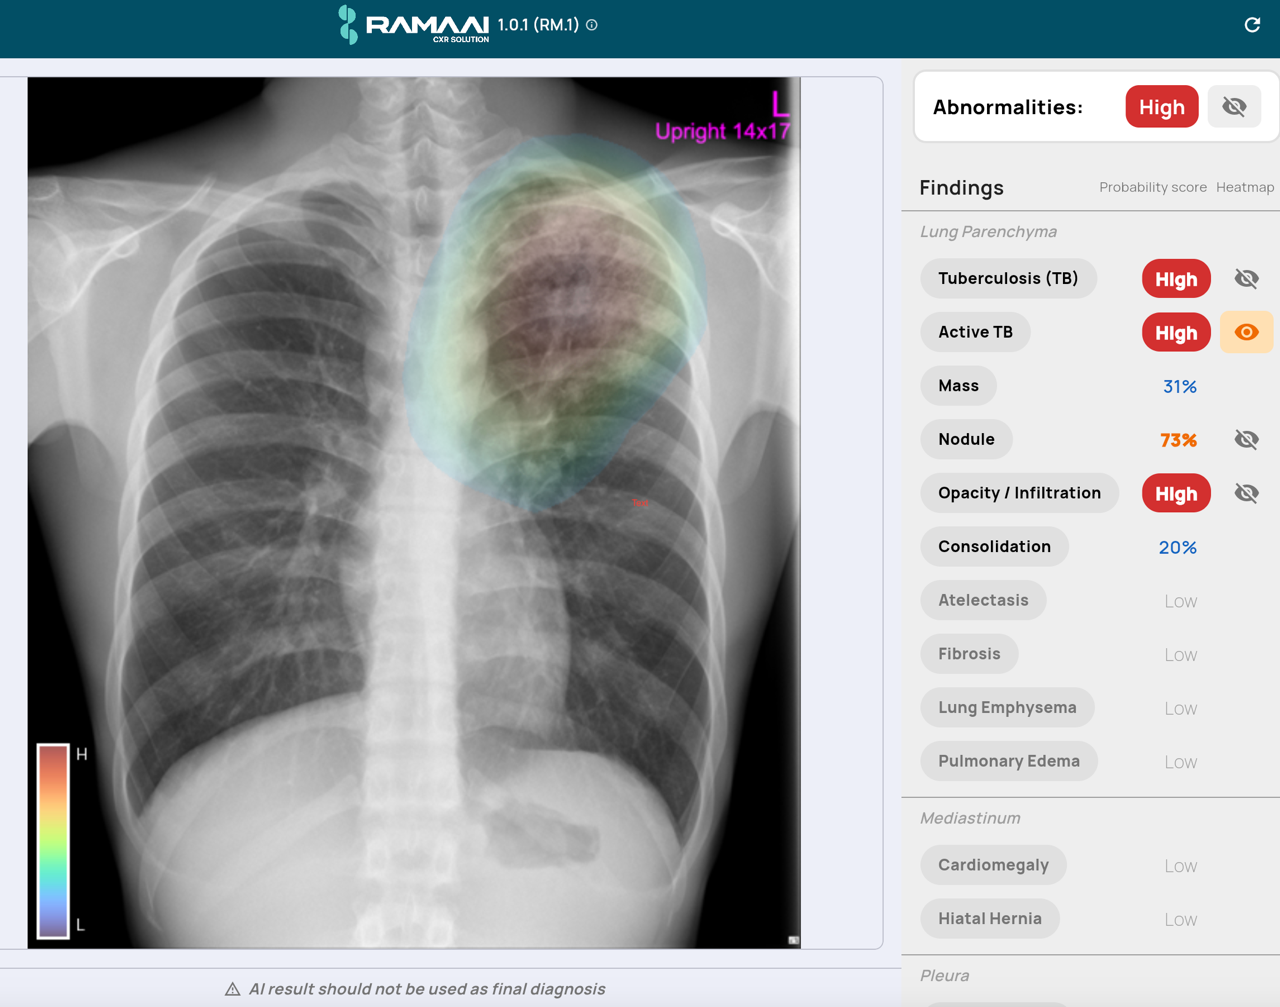

RAMAAI CXR Solution ในเวอร์ชันปัจจุบันสามารถช่วยคัดกรองและชี้แนะความผิดปกติบนภาพเอกซเรย์ทรวงอกได้ถึง 16 ภาวะ ครอบคลุมกลุ่มโรคที่พบบ่อยและมีความสำคัญเชิงสาธารณสุขของประเทศไทย อาทิ วัณโรคปอด ที่เป็นจุดบอดของ AI ต่างชาติส่วนใหญ่, ก้อนและรอยโรคที่สงสัยมะเร็งปอด ซึ่งการตรวจพบในระยะแรกส่งผลโดยตรงต่ออัตราการรอดชีวิต, ภาวะปอดอักเสบและการติดเชื้อในปอด ซึ่งเป็นสาเหตุการเสียชีวิตอันดับต้นของผู้สูงอายุไทย, ภาวะหัวใจโตและสัญญาณของภาวะหัวใจล้มเหลว, ภาวะถุงลมโป่งพองและภาวะปอดแฟบ, ภาวะลมรั่วและน้ำในช่องเยื่อหุ้มปอด

จุดที่ทำให้ RAMAAI แตกต่างจากผลิตภัณฑ์ AI CXR ในตลาดโลก คือโมดูลที่เรียกว่า “Zero TB Module” ความสามารถในการตรวจจับวัณโรคในระยะแพร่กระจาย (active tuberculosis) ซึ่งเป็นภาวะที่แม้แต่รังสีแพทย์ที่มีประสบการณ์ก็ยังวินิจฉัยยาก และเป็นช่องว่างที่ระบบ AI เชิงพาณิชย์จากต่างประเทศแทบไม่มีใครเข้าไปแตะ เพราะข้อมูลฝึกสอนในประเทศต้นทางไม่เพียงพอ